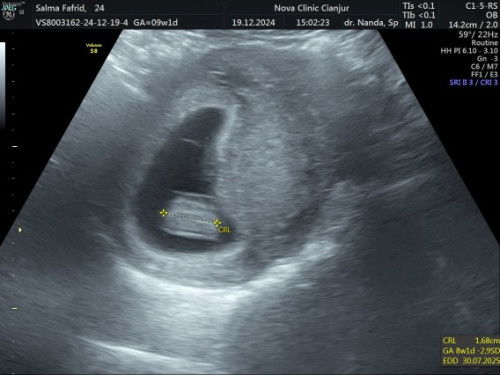

Setelah usg ulang di dokter SpOG, Alhamdulillah akhirnya terlihat kantung dan janin nya bahkan djj nya pun sudah ada, dan usia nya ternyata baru 8w, beda 1 minggu dari perkiraan hpht , terimakasih bunda bunda yang sudah memberikan saran dan masukannya, akhirnya bisa tenang, sehat selalu semuanya🤗